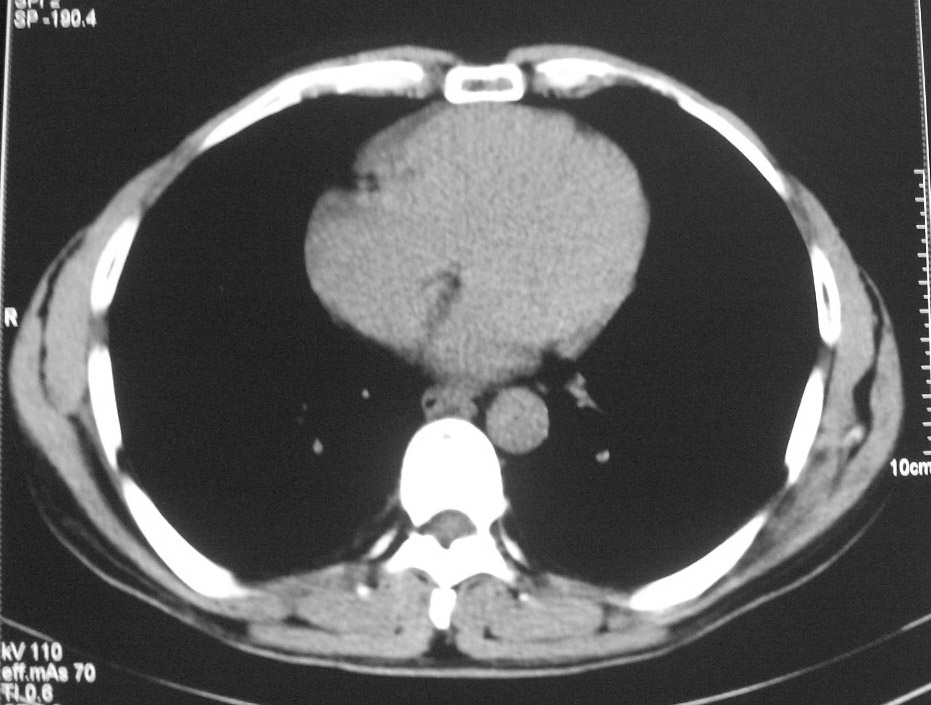

标题: CT5485:[原创]肺部占位请讨论

右肺上叶中央型肺癌并上叶肺不张、纵隔淋巴结肿大

右上叶支气管肺癌并右上叶阻塞性不张,右侧少量胸腔积液.

右上肺中央性肺癌伴右侧胸腔少量积液!右上肺胸膜下还有一小病灶,不完全排除结核,但个人支持恶性肿瘤!建议早穿刺活检。

右肺上叶中央型肺癌并上叶肺不张、纵隔淋巴结肿大.右侧少量胸腔积液。

右上肺中心型肺癌并肺不张,纵膈淋巴结肿大。右侧少量胸腔积液。

右肺上叶不张,考虑中央型肺癌。右侧胸膜肥厚

右肺上叶中央型肺癌并阻塞性炎症、阻塞性肺不张……